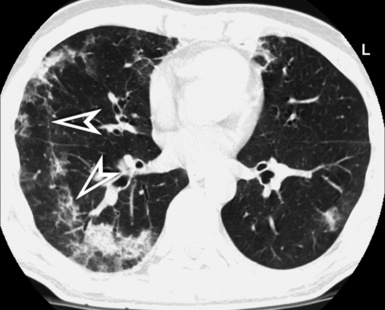

These are mixed densities and tree-in-bud entities. Single or multiple areas of consolidation/GGO alert to the existence of an alveolar disorder.67 Signs of bronchial and bronchiolar involvement (bronchiectasis and bronchial wall thickening, bronchiolectasis with tree-in-bud or centrilobular nodules) often coexist and at times are the dominant pattern.66,67,70 In areas of bronchiolar involvement, expiratory air trapping is frequently evident.67,70 Cavitated opacities should raise the possibility of mycobacterial disease, and a surrounding (but also at a distance) tree-in-bud pattern should raise the suspicion of an aerogenous spread of disease (Fig. 3-135).

Bronchiolitis of infectious origin often has a patchy distribution, whereas noninfectious, inflammatory bronchiolitis tends to have a more uniform, bilaterally symmetrical involvement. Diffuse panbronchiolitis, in particular, presents with centrilobular nodules, tree-in-bud pattern, bronchiectasis, and bronchiolectasis with a dominant symmetrical lower lobe distribution.67 If signs of bronchial involvement (including bronchiectasis) and/or alveolar opacities are found predominantly in the right middle lobe and lingula, an infection from nontuberculous mycobacteria (“Lady Windermere” syndrome) should be suspected153–155 (Fig. 3-136).